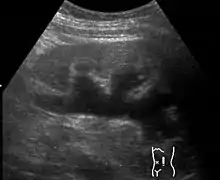

| Renal ultrasonography of hydronephrosis caused by a left ureteral stone. | |